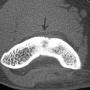

Kemik üreten selim bir kemik tümörüdür. Sıklıkla 10 - 20 yaşları arasındaki erkeklerde görülür. Ana şikayet zonklayıcı, genellikle geceleri artan ve uykudan uyandırabilen, aspirin ile geçebilen bir ağrıdır. Bazı hastalar, ağrı nedeni ile uzvunu kullanamama, buna bağlı eklem hareket kısıtlılığı ve şekil bozukluğu (kontraktür), uzuvda incelme, omurgada eğrilik gibi şikayetler ile başvurur. En sık femur boynunda ve tibiada olmakla birlikte tür kemiklerde ortaya çıkabilir. Lezyonun karakteristik özelliği düz grafide litik görülen bir çekirdek (nidus) ve bunun etrafında yoğun kemik oluşumu ile karakterize sklerotik bir halkadır. MRG, nidus çevresinde ve bazen yumuşak dokuya taşan ödemi abartarak gösterdiği için çoğu zaman daha korkutucu tanıları düşündürebilir. Sintigrafi odaksal bir tutulum ve ortasında tutulum olmayan bir nokta gösterecektir. Osteoid osteoma için en değerli ve hassas tanı koydurucu yöntem, bilgisayarlı tomografidir. İnce kesitli (en fazla 2 mm) BT incelemesinde nidus ve çevresindeki skleroz tipik olarak gösterilebilir.